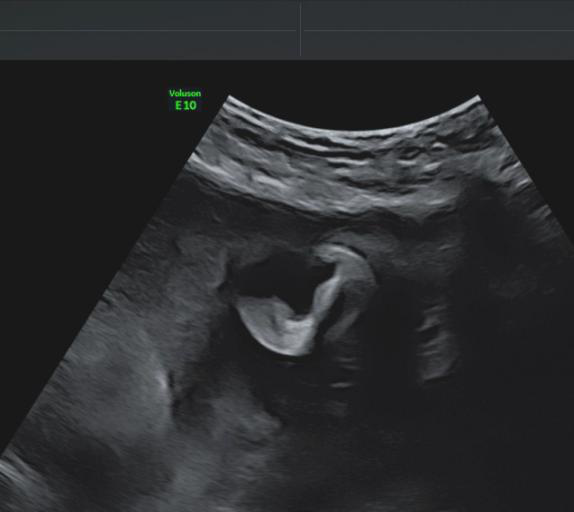

得益于煊光成像技术,胎儿在子宫中的样子非常清晰

一台专业优秀的妇产超声机,对于产前胎儿四维超声筛查、子宫双侧附件及女性盆底功能障碍性疾病检查需要具备高端专业的处理机制。GE Voluson E10 BT20金标版在原有高端平台的基础上搭载了全新的煊光成像平台、煊影成像技术和煊流成像技术,能够360°高清立体、超真动态地显示宝宝的实时活动图像,创新性的二维立体血流成像模式Radiant flow、超低速血流成像模式 SlowflowHD即便是微小的血管也能轻松的快速显现,提高了血流的视觉敏感性,卓越的图像质量,大大提高了临床诊断的准确率。

卓越的二维图像图像质量